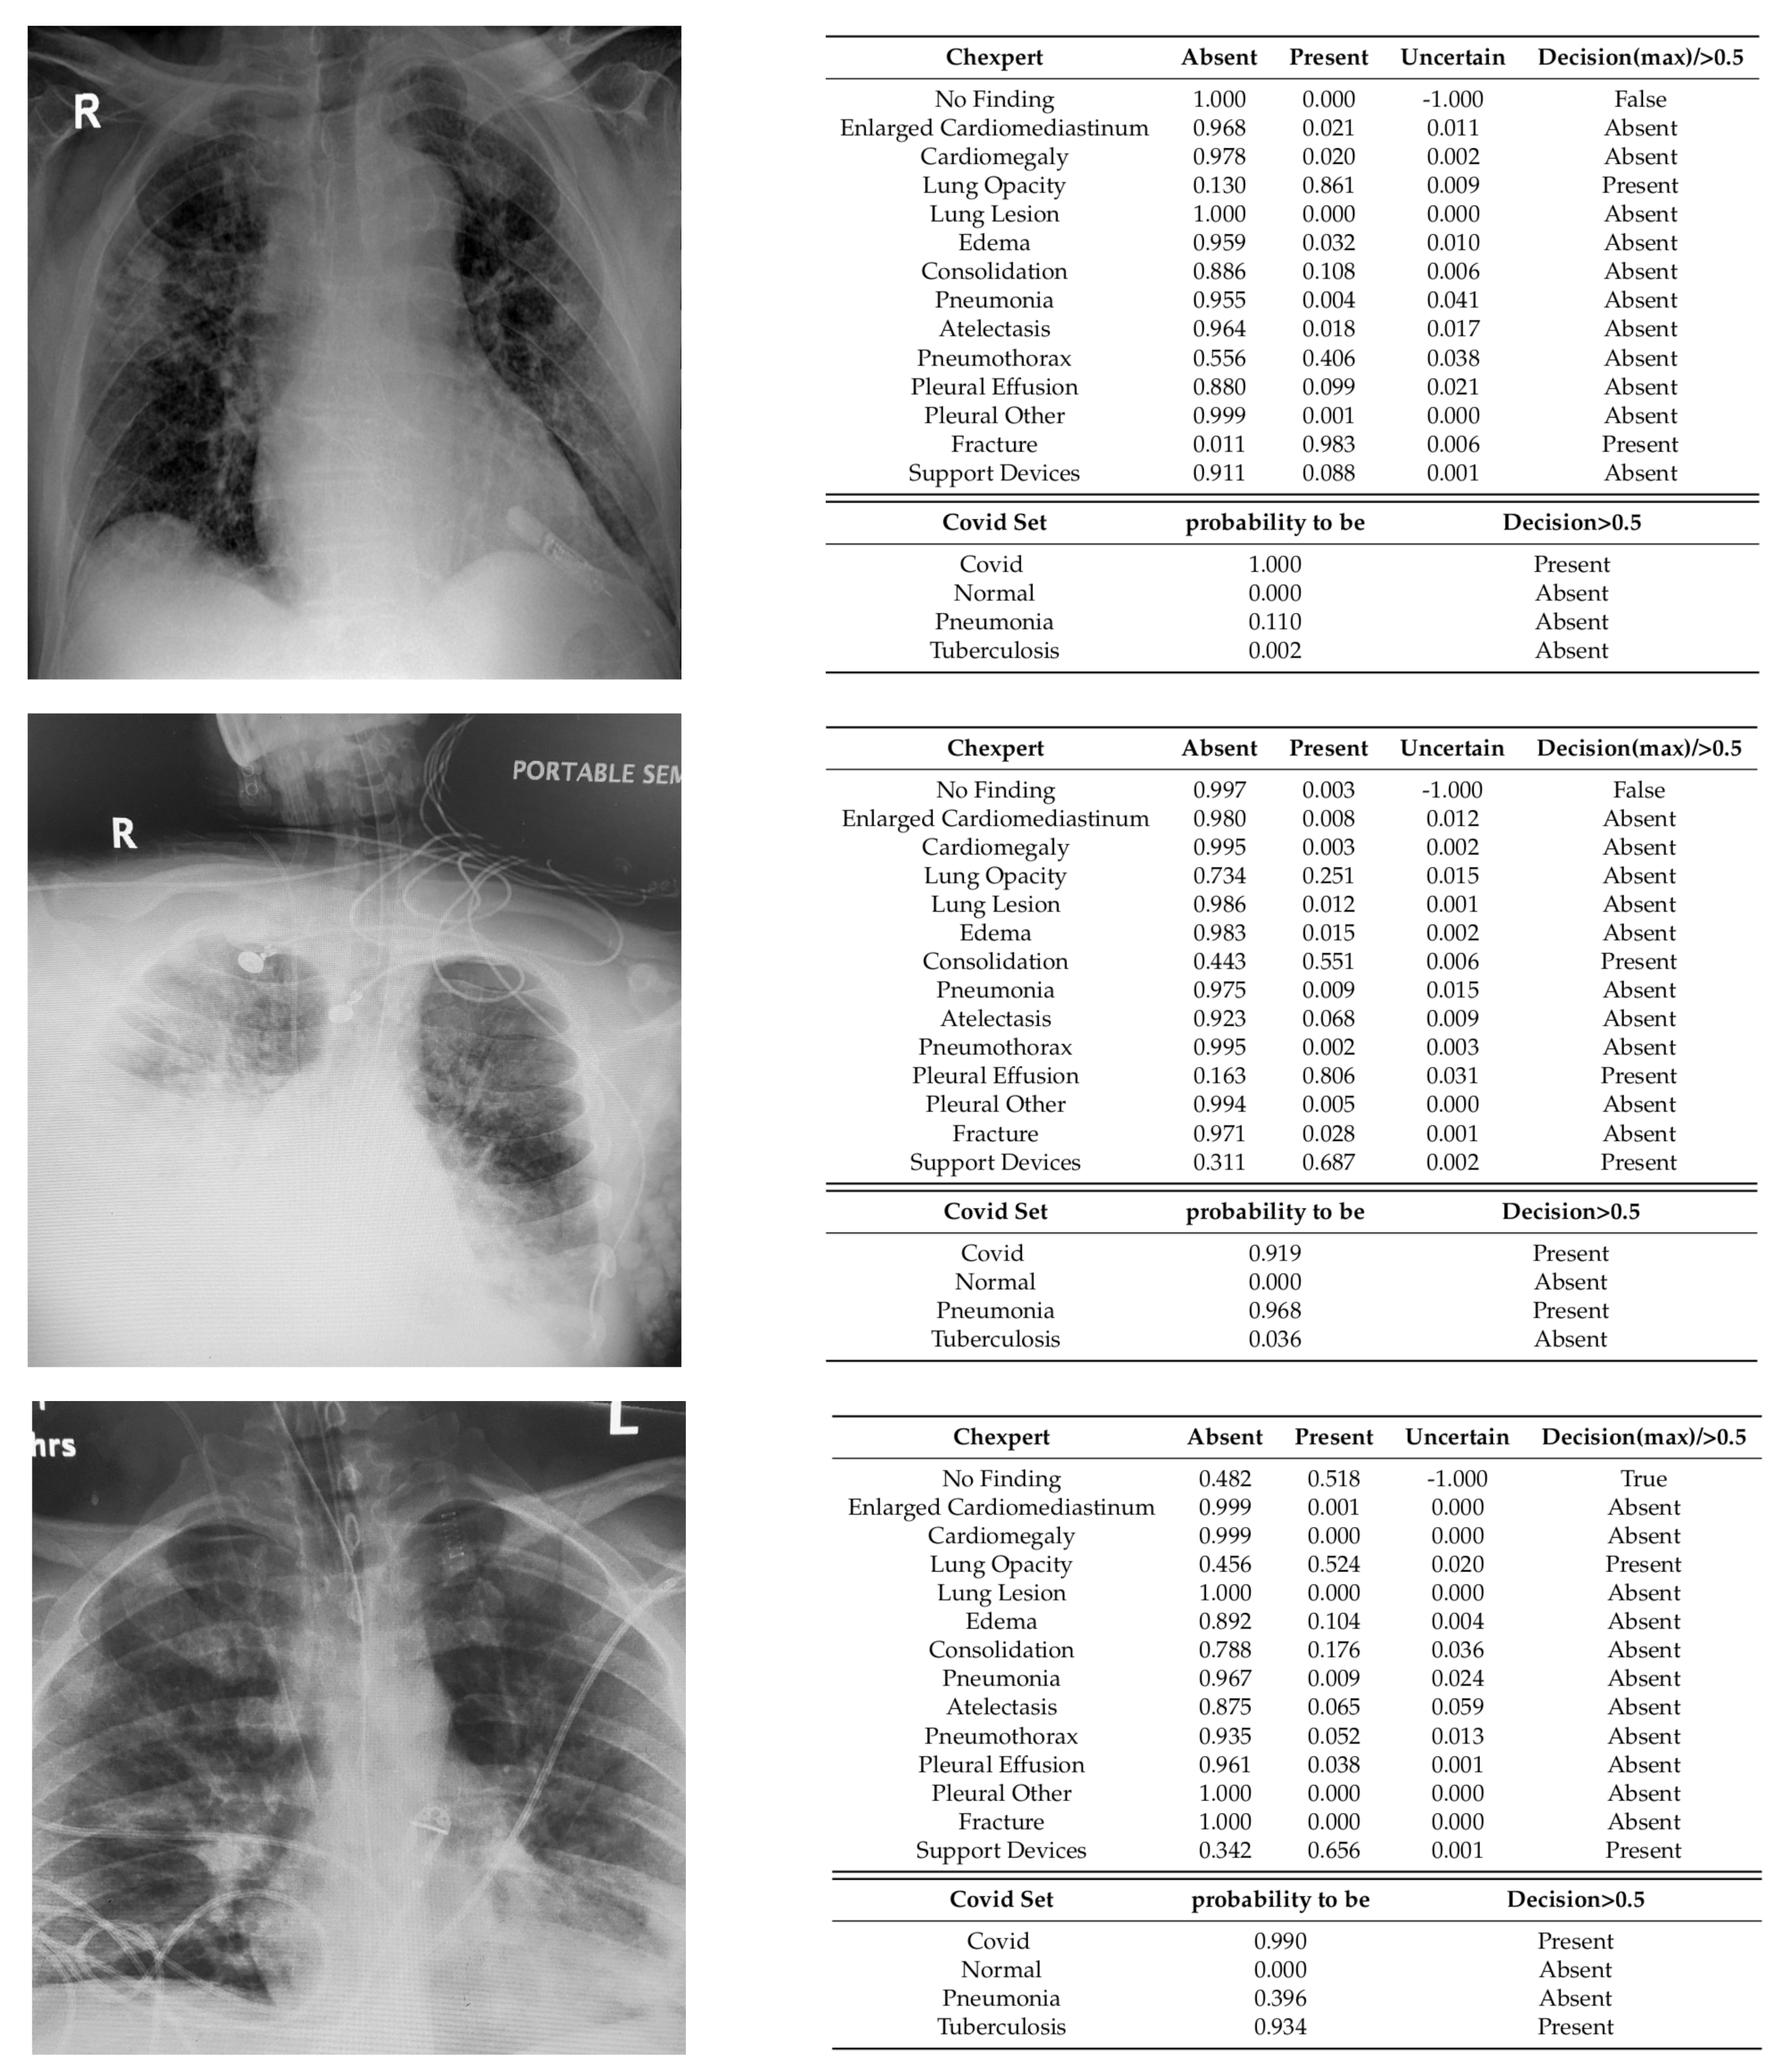

To go beyond the numerical evaluation, we applied our models on a set of X-rays from a different set, COVID-Net, and we analyzed the results together with two radiologists. We detail here the 14 observations predicted by the CheXpert-14 model, together with the predictions of the model CheXpert-COVID19 for the 4 class (Figure 10).

Figure 10.

Three predictions of CheXpert-14 and CheXpert-COVID19 models on representative X-rays of COVID-19 patients; public available images from COVID-net dataset [19].

In the first example from Figure 10, all the predictions are correct, except the one for the fracture.

In the second example, even though the X-ray images are over-saturated at the bottom, the presence of consolidation and pleural effusion are correct, together with the decision for COVID-19. The prediction for pneumonia is wrong if we consider pneumonia to be the non-COVID pneumonia.

The third example is correctly classified as COVID-19, but the probability of having tuberculosis is too large (0.797). The probability of “No finding” is , which wrongly asserts the image to be without abnormalities (even though it is quite close to the threshold). The model correctly identifies the presence of the support device and the lung opacity.

According to the qualitative analysis, even though the quality of the predictions improved after using the 2-phase training with CheXpert compared to a training without CheXpert, there is still room for improvement. The most important limitation remains the small number of samples for COVID-19-positive.